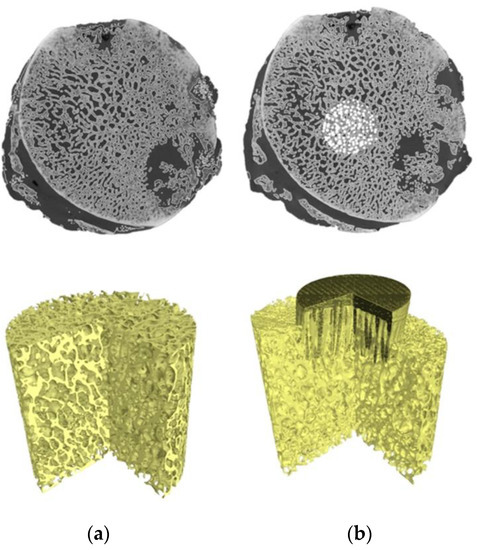

2.7. Micro-CT 3D Reconstruction of Specimens

- Uklejewski, R.; Winiecki, M.; Patalas, A.; Rogala, P. Bone Density Micro-CT Assessment during Embedding of the Innovative Multi-Spiked Connecting Scaffold in Periarticular Bone to Elaborate a Validated Numerical Model for Designing Biomimetic Fixation of Resurfacing Endoprostheses. Materials 2021, 14, 1384. [Google Scholar] [CrossRef] [PubMed]